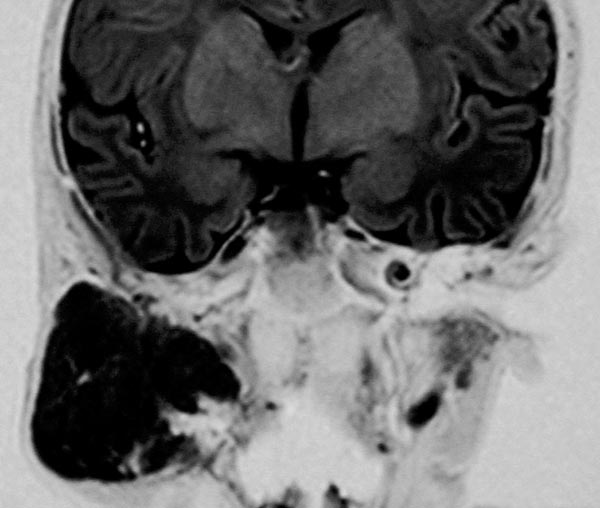

Die koronare Inversion-Recovery-Sequenz (MRT) zeigt nochmals sehr gut die Ausdehnung des Hämangioms. Die Signalgebung ist isointens zum Hirngewebe. Es handelt sich klar um eine solide Raumforderung.